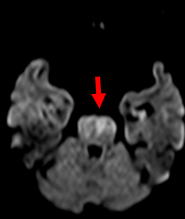

2例目を紹介いたします。81歳女性、自宅にて意識がなく、倒れているところを発見されました。来院時、JCS200と重篤な意識障害、左共同偏視、右片麻痺を認めました。頭部MRIにて脳幹に淡い梗塞、(図1)MRAにて脳底動脈の閉塞を認めました。(図2)再開通しなければ、死亡率が高い病態です。緊急にて血管撮影を行い、脳底動脈の閉塞を認めました。(図3)Penumbra吸引カテーテルと血栓除去用ステント(Trevo provue 4×20mm)を用いて血栓除去を行い、TICI3の完全再開通を認めました。(図4)翌日のMRIでは脳幹に梗塞を認めるも、(図5)意識障害は急速に改善しました。超高齢なために、約2ヶ月間のリハビリテーションを経て自宅へ戻りました。

![]() 図1:MRI拡散強調画 一部脳幹に淡い虚血を認めます。 |